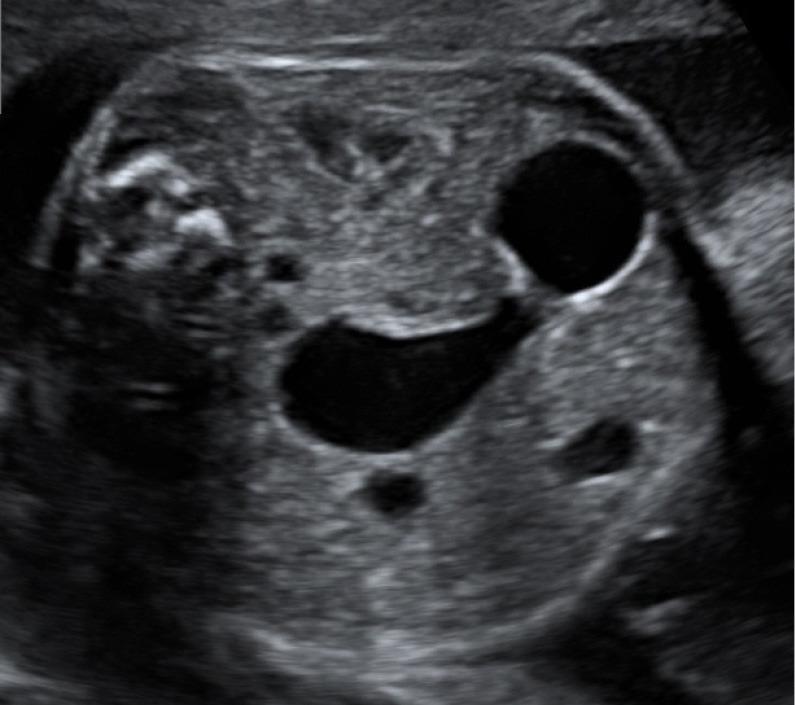

Congenital heart disease (CHD) is the most common cause of major congenital anomalies affecting newborns. Prenatal detection of CHD has been improving continuously during the last two decades due to technical advances and thus optimized fetal cardiac imaging. Besides the in-utero diagnosis of CHD effective parental counseling is an integral part of any Fetal Cardiology Program. However, studies on the most effective techniques are scarce, as well as data on empirical assessment of counseling and its effectiveness. In this review article, we summarize current guidelines from different international associations and societies. We provide an updated literature overview evaluating current standards of counseling with regard to parental needs. This includes ethical aspects, counseling for univentricular disease and in-utero cardiac interventions. We discuss our method to assess counseling success for fetal heart defects by exploring different analytical dimensions that may be considered helpful in order to improve efficacy. Finally, we present a proposal of how to optimize a setting for counseling based on the current literature and our own data. In summary, parental counseling for fetal heart disease is complex and multidimensional. Significant expertise in fetal cardiology and physiology, potential progression of CHD, postnatal treatment strategies and knowledge of long-term sequelae is necessary. A structured approach, together with continuous improvement of communicative skills, may lead to more effective counseling for parents following a diagnosis of CHD in the fetus.

先天性心脏病(CHD)是影响新生儿的主要先天性异常的最常见原因。在过去二十年中,由于技术进步以及胎儿心脏成像技术的优化,CHD的产前检测一直在不断改善。除了在子宫内诊断CHD外,有效的父母咨询是任何胎儿心脏病学项目不可或缺的一部分。然而,关于最有效技术的研究很少,关于咨询的实证评估及其有效性的数据也很少。在这篇综述文章中,我们总结了不同国际协会和学会的现行指南。我们提供了一份最新的文献综述,评估了关于父母需求的咨询现行标准。这包括伦理方面、单心室疾病咨询和子宫内心脏干预。我们通过探索不同的分析维度来讨论我们评估胎儿心脏缺陷咨询成功与否的方法,这些维度可能有助于提高咨询效果。最后,我们根据当前文献和我们自己的数据提出了如何优化咨询环境的建议。总之,胎儿心脏病的父母咨询是复杂且多维度的。胎儿心脏病学和生理学、CHD的潜在进展、产后治疗策略以及长期后遗症知识方面的专业知识是必要的。一种结构化的方法,加上沟通技巧的不断提高,可能会为胎儿被诊断为CHD的父母带来更有效的咨询。